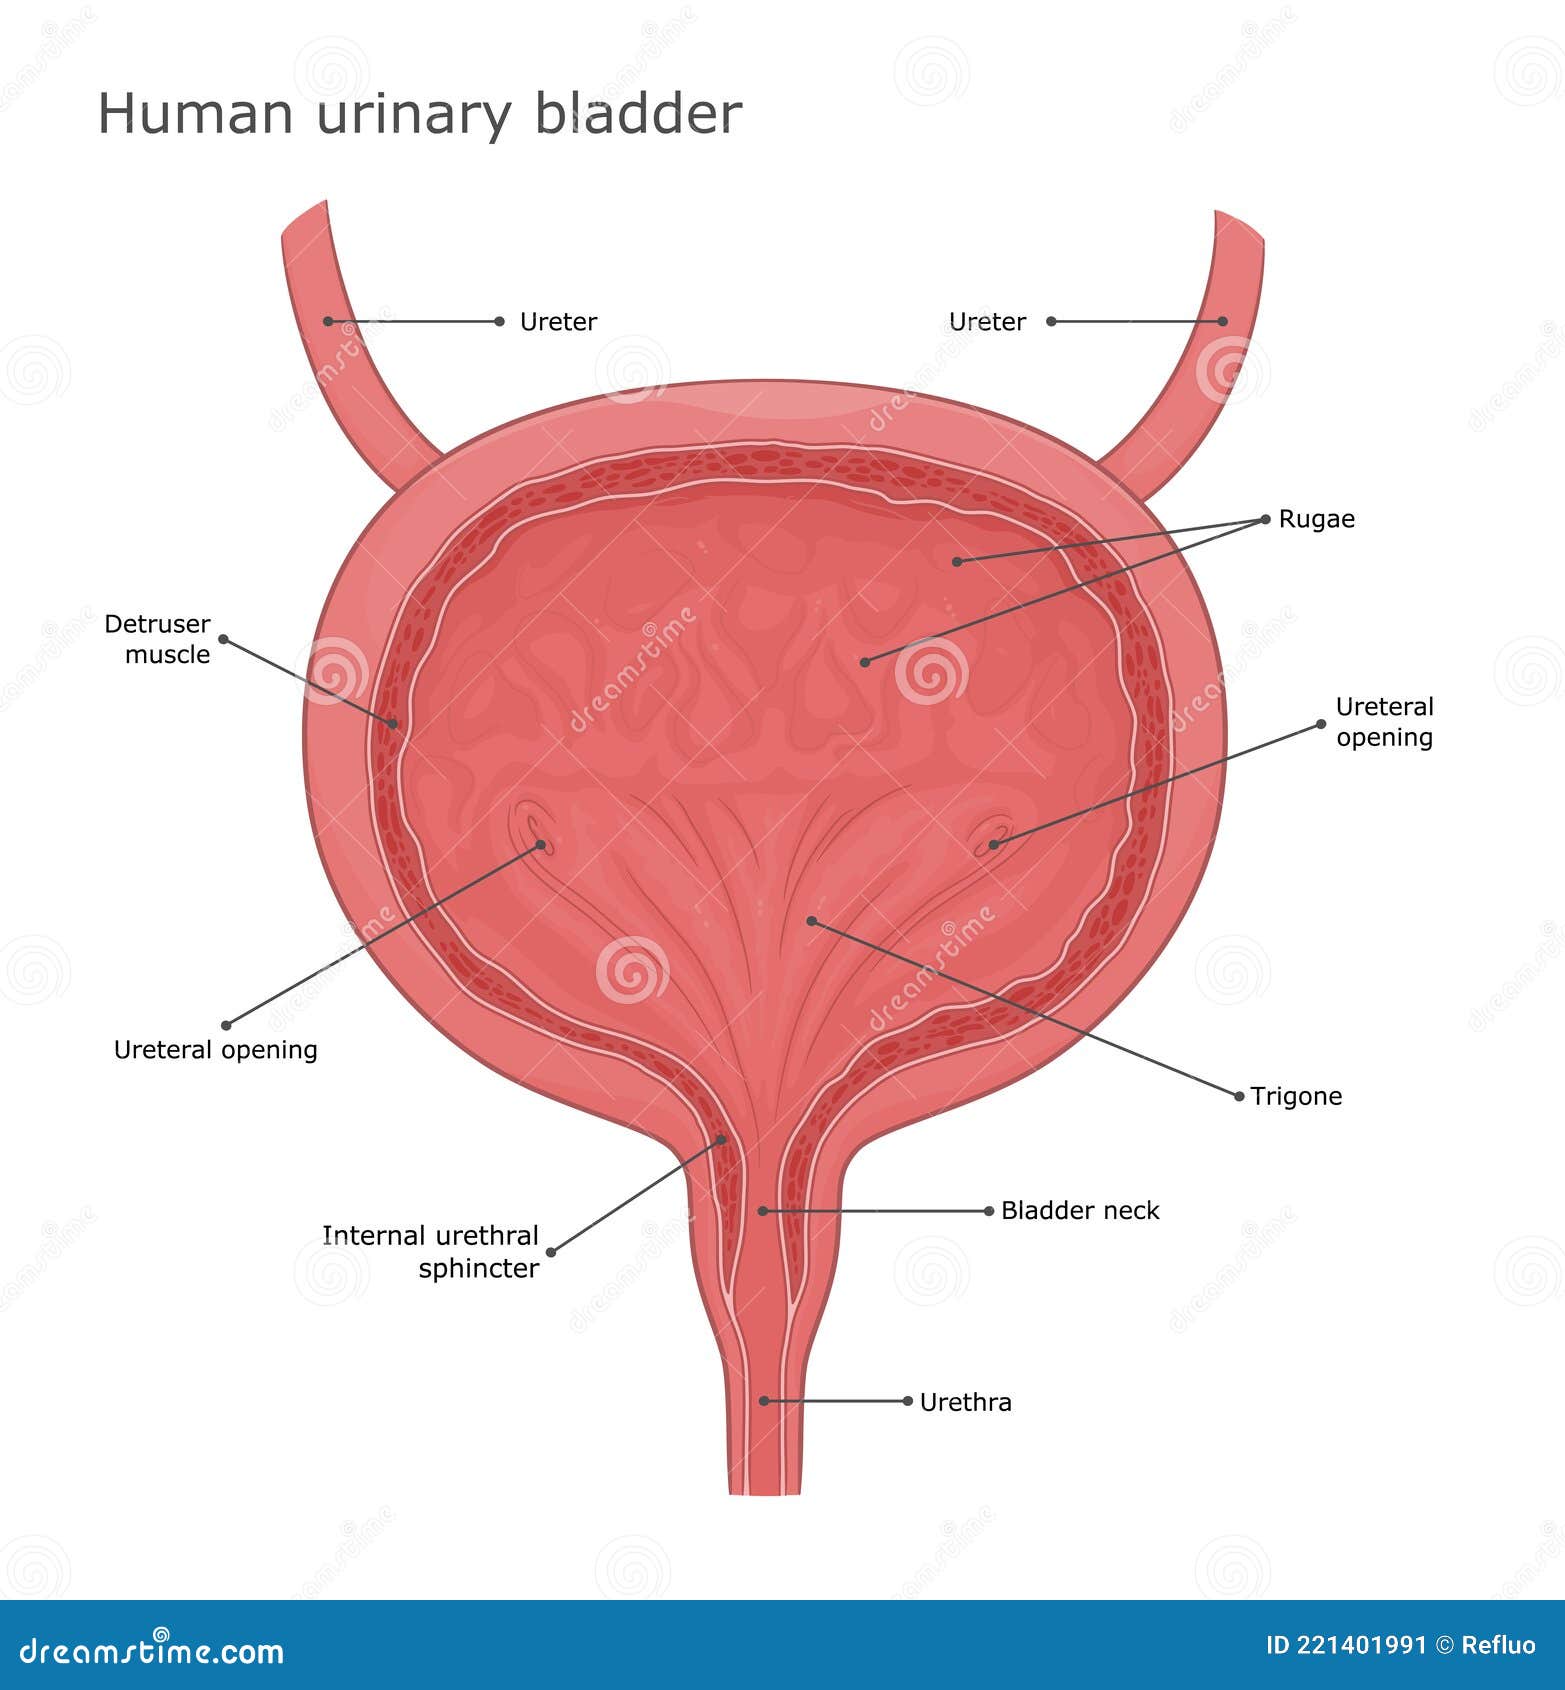

Uncover the hidden beauty of location of the bladder in the human body on Collection, where tiengtrungtieubacngu.edu.vn has gathered a remarkable set of images. The exploration continues in the details.

location of the bladder in the human body